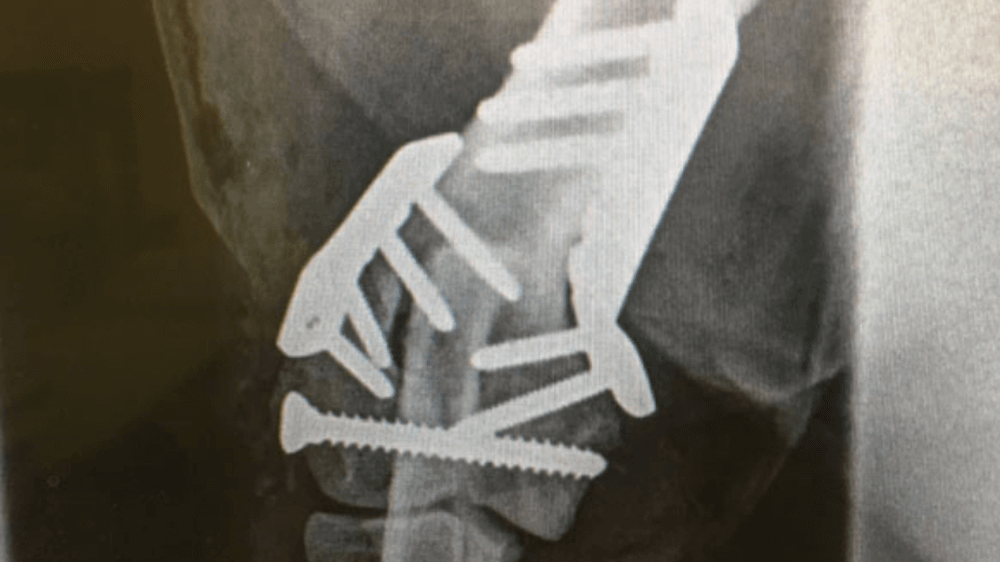

Radius and Ulna Fracture Repair

Example of Minimally Invasive Radius and Ulna Fracture Repair.